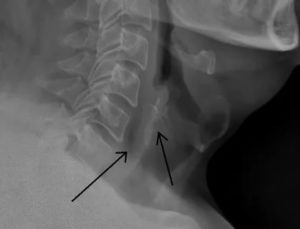

В большинстве случаев бывает сложно определить место локализации кости. Если она застряла между ротоглоткой и гортаноглоткой, то возникают не локальные, а разлитые болевые ощущения. Чтобы обнаружить кость в пищеводе, необходимо провести эндоскопическое исследование.